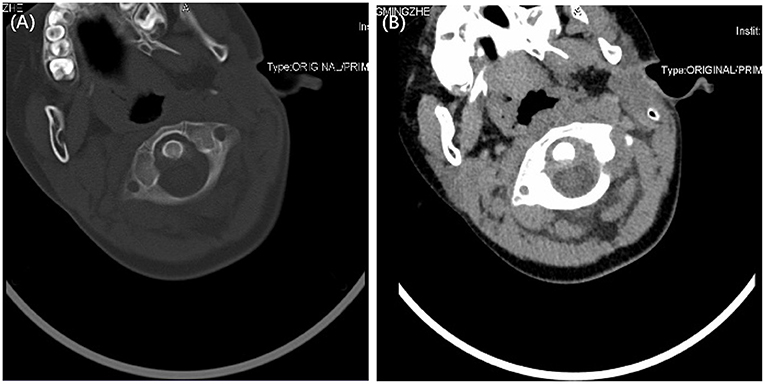

CT scan (Computed Tomography): The diagnostic gold standard for confirming atlantoaxial subluxation. It precisely demonstrates the degree and direction of displacement.

● MRI (Magnetic Resonance Imaging): Useful for assessing soft tissue inflammation, ligamentous injury, and spinal cord involvement.